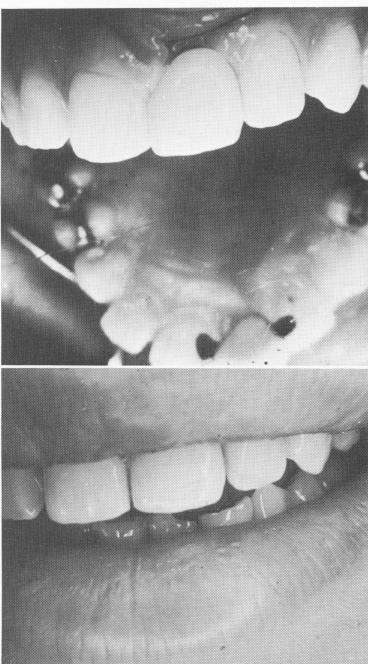

Fig. 11-31. A single tooth restoration. A, Labial view showing slight overlapping of interproximal surface. B, With two gold lingual rests.

1 Maxillary labial view showing overlapping of interproximal surface

2 Maxillary crown fabricated with lingual gold rest seats